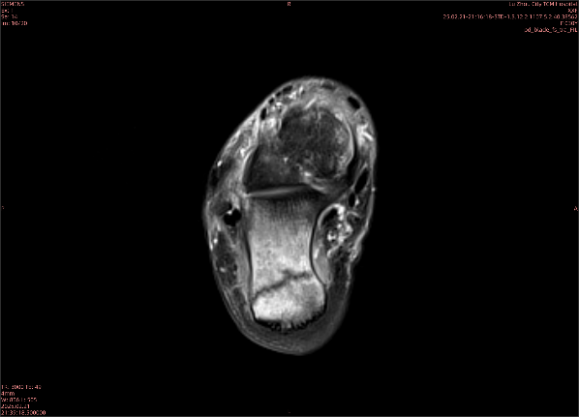

隱性骨折在MRI表現(xiàn)為T(mén)1WI序列上見(jiàn)由關(guān)節(jié)面向骨干走行的形態(tài)各異低信號(hào)區(qū),有線狀、條狀、紊亂低信號(hào),信號(hào)強(qiáng)度不均勻。與T1WI低信號(hào)改變相對(duì)應(yīng)部位在T2WI上表現(xiàn)為相應(yīng)形狀的高、低混雜信號(hào),且部分低信號(hào)周?chē)梢?jiàn)高信號(hào)水腫改變。STIR序列圖像上病灶呈顯著高信號(hào),與信號(hào)被抑制的臨近正常骨髓形成鮮明對(duì)比,分界也較T2WI成像更為清楚。脂肪組織抑制技術(shù)是MRI的一個(gè)重要性能,脂肪抑制技術(shù)在MRI應(yīng)用中可以改善組織對(duì)比和增加病變顯示機(jī)會(huì),這樣骨髓的脂肪抑制后就不會(huì)有任何信號(hào),而隱性骨折線及骨髓水腫的異常高信號(hào)就會(huì)更加明顯的顯示出來(lái)。

舉例圖像

圖1

專(zhuān)業(yè)解釋看不懂沒(méi)關(guān)系,大家看圖1和圖2就可以了,這是同一個(gè)患者跟骨的磁共振和CT圖像,圖1的紅色箭頭指示的黑線就是磁共振圖像顯示的骨折線,一目了然。而對(duì)比圖2的CT圖像上并未顯示異常。